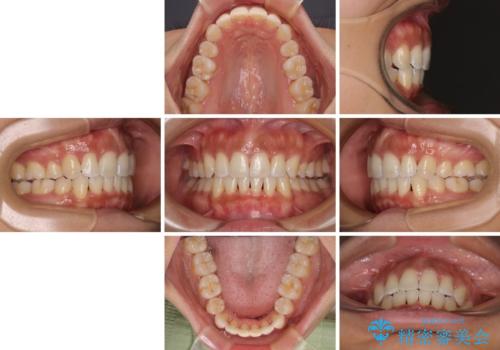

抜歯矯正で唇を閉じやすく 目立たないワイヤー装置

- 下唇が突き出るような口元の突出感が気になるとのことで来院された患者様です。

上下顎ともに前突した歯列であったので、上下ともに左右の第1小臼歯4本を抜歯し、ワイヤー装置にて矯正治療を行うこととしました。

抜歯スペースに前歯を移動させることで歯の突出感が改善され、非常に唇が閉じやすい仕上がりとなりました。